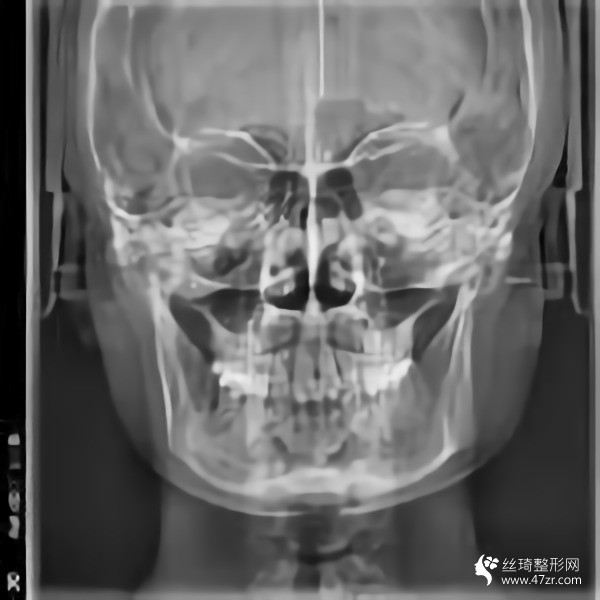

金柱翰院長韓國頜面整形專家、韓國鼻整形專家、下頜角截骨術(shù)技術(shù)專家、韓國“微整形技術(shù)研究”專家,多次接受記者采訪,南京醫(yī)科大學國際整形教學研究中心副主任,南京醫(yī)科大學友誼整形醫(yī)院專家委員會常委;擅長鼻整形手術(shù):自體鼻中隔軟骨移植隆鼻,耳軟骨移植隆鼻,肋骨移植隆鼻,假體隆鼻,鼻尖鼻翼整形手術(shù),各種畸形鼻的矯正,隆鼻失敗的修復,歪鼻的矯正;

從高中開始,人們就一直說我的臉很方。就算不直接說臉,我也會說臉很大。每次聽到心里都很無奈,臉上都在埋怨我...每次我回嘴的時候,也是一副滿不在乎的表情。然而,我的心還是不自覺地開始關心它。說白了,我要小一點的臉。其實我一直有做下頜角的想法。之前我還在讀書,沒錢?,F(xiàn)在出來工作了,經(jīng)濟獨立了,咨詢了醫(yī)院說可以,終于可以解決這個大面子問題了

手術(shù)后15天。過來拆線。反正我覺得我更喜歡自己。一點都好看。看起來很可愛。目前有點腫,但輪廓線條開始慢慢顯現(xiàn)。畢竟拆線?;謴蜖顟B(tài)還是很滿意的。目前較重要的是照顧好自己。父母不在身邊。我還沒有過恢復期。我不能吃得太隨便。我必須注意我的飲食。這個真的是先苦后甜。不過為了后面的恢復果,一切都是值得的

回來快一個月了,基本沒有腫脹,輪廓清晰柔和。不知道是不是錯覺,感覺皮膚細膩多了。哈哈,雖然有美顏加持,但是大家看不出來很正常,但是可以自己感受一下。院長的技術(shù)真的很好,不愧是變臉王。剛來的時候看到幾個美女好像是花錢磨骨頭的,表現(xiàn)的多火啊。合格的醫(yī)生就是不一樣,讓人安心。醫(yī)院里的人手術(shù)后一直在回來康復。說起來有點太熱情了,讓我不敢接電話。

我又來了。我不記得上次是多久了。年紀大了記憶力下降了很多,但身邊認識的很多人也會這樣。好像沒有明X的辦法。再說說我的下頜角手術(shù)。雖然手術(shù)的時候感覺不深,但是手術(shù)后確實記得很深,總是需要經(jīng)歷一些徹骨的寒冷,梅花才會有香味。較近的照片給你們發(fā)一波,如果手術(shù)做的好那么你以后就不會后悔了。

在生活中,我們往往忘記了健康和鍛煉,大多數(shù)人會在自己的世界里沉默,但生活中的許多實際問題仍然會把你拉回現(xiàn)實。我其實很喜歡去健身房,但是是時間問題導致我沒能得到我想要的。另外,我在下頜角休息了很久,臉部好了很多,運動還是不可或缺的。其實我覺得健康較重要,其次是外表和對自己的信任,哈哈